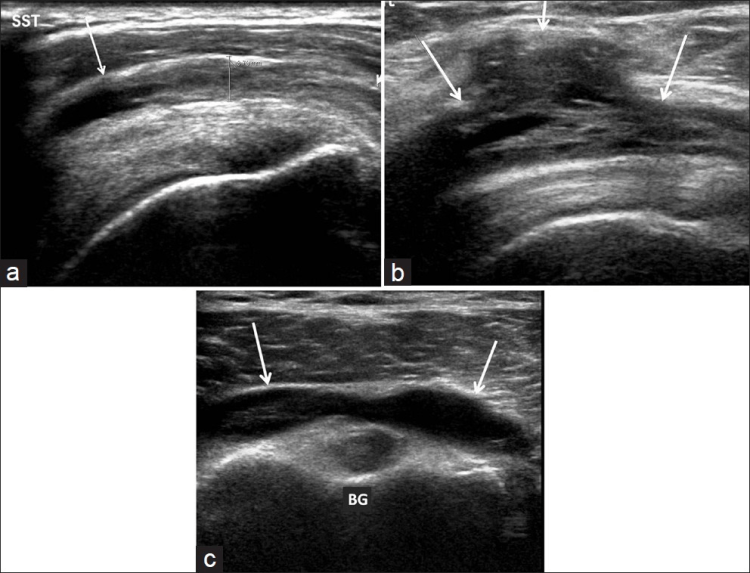

La ecografía del hombro comienza examinando el surco bicipital (BG) y la cabeza larga del tendón del bíceps braquial. El paciente está sentado frente al operador en una posición neutra, su mano colocada con la palma hacia arriba sobre el muslo. Se realiza una imagen de eje corto colocando el transductor sobre la metáfisis humeral proximal perpendicular al húmero. La imagen del eje largo del tendón se obtiene girando el transductor a una posición paralela a la diáfisis humeral [Figura 1]. Luego, se examina el tendón del subescapular. El brazo del paciente se fija sobre el flanco y el antebrazo se abduce en rotación externa. Se realizan vistas de eje largo y corto del tendón [Figura 2]. Los tendones infraespinoso y redondo menor se examinan desde una vista posterior del hombro. El paciente se gira 90°, su mano se coloca sobre el hombro opuesto y el transductor se orienta en el plano axial sobre la cabeza del húmero [Figura 3]. La articulación glenohumeral y la escotadura espinoglenoidea también se examinan en una vista posterior del hombro. El transductor ahora se mueve medial y caudalmente en el plano transversal hasta que se vea el margen posterior de la articulación glenohumeral y luego, más medialmente para mostrar la escotadura espinoglenoidea [Figura 4]. El tendón supraespinoso se escanea en una vista anterior del hombro. El paciente está sentado frente al operador. El brazo del paciente se coloca en una posición posterior, la mano dorsal en el ala ilíaca opuesta o la mano palmar en el ala ilíaca ipsilateral. Se obtienen vistas de eje largo y corto del tendón supraespinoso. Luego se realiza la exploración del manguito de los rotadores durante las maniobras dinámicas. El transductor se coloca sobre el acromion. El brazo del paciente se abduce con el codo flexionado a 90° o/y el brazo se extiende anteriormente [Figura 5]. Finalmente, se escanea la articulación acromioclavicular. La mano del paciente se coloca con la palma hacia arriba sobre el muslo. El transductor se coloca sobre la parte superior del hombro en un plano coronal [Figura 6].